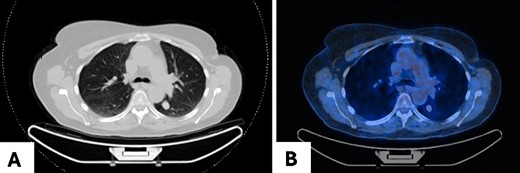

A 68-year-old woman was referred to our clinic for surgical evaluation after abnormal findings on a computed tomography (CT) scan (Fig. 1A). She had a history of breast cancer for which she underwent surgical resection and local lymphadenectomy in 2005. Despite being asymptomatic, and nearly two decades later in 2024, her CT scan revealed a well-defined 1.5-cm lesion in segment VI of the left lower lobe. A subsequent PET-CT scan (Fig. 1B) showed minimal metabolic activity in this area, and no further abnormalities. Initially, the lesion was suspected to be a hamartoma, with lung carcinoma considered as a potential alternative diagnosis.

Pulmonary meningioma in segment VI of the left lower lobe in axial view in (A) CT scan showing a well-circumscribed/bordered homogenous, solid, noncalcified lesion; (B) PET-CT scan showing minimal metabolic activity.